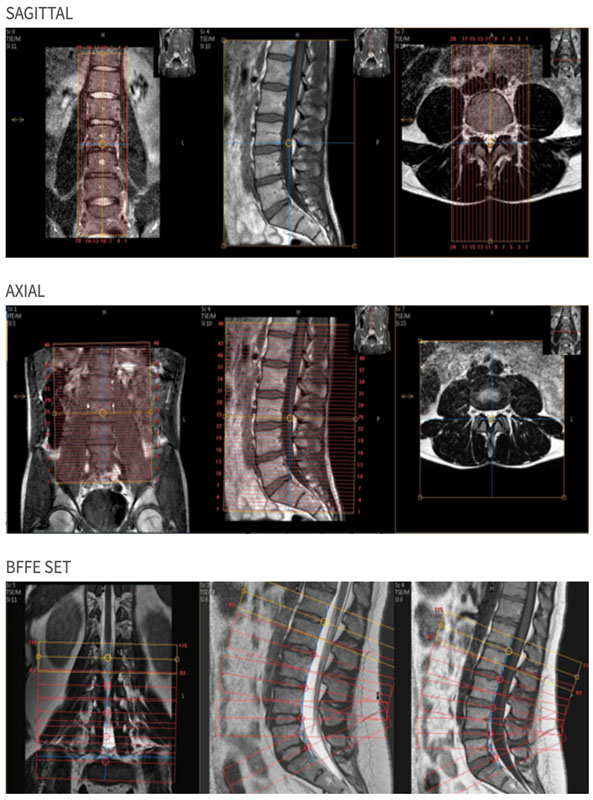

| Plane | Weighting | Mode | Slice | Gap | FAT SAT | FOV | Notes |

|---|---|---|---|---|---|---|---|

| SAG | T2 DRIVE | TSE | 3mm | 0.5mm | None | 25cm | Lateral Sides of Vertebral Bodies |

| SAG | T1 | TSE | 3mm | 0.5mm | None | 25cm | Lateral Sides of Vertebral Bodies |

| SAG | STIR | TSE | 3mm | 0.5mm | STIR | 25cm | Lateral Sides of Vertebral Bodies |

| DISKS | T2 MULTISTACK | TSE | 3mm | 0mm | None | 15cm | Cover Disk Spaces L1-L5. Do not change number of slices. |